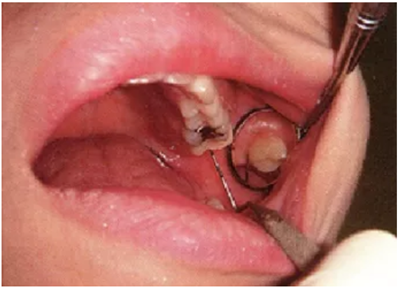

上頜第二后磨牙頰側(cè)遠(yuǎn)中的檢查技巧

上頜第二后磨牙的頰側(cè)遠(yuǎn)中檢查難度特別高。探針插入本身難度很高,還要讀取數(shù)值,非常艱難。這個(gè)部位的檢查頁和上面頰側(cè)檢查一樣讓患者嘴巴微閉,利用口鏡可以比較容易讀取數(shù)值。

● 利用口鏡對(duì)上頜第二后磨牙頰側(cè)遠(yuǎn)中檢查時(shí),患者嘴巴也需要微閉。

微閉嘴巴,頰粘膜跟容易延展,將口徑放入嘴巴時(shí)可以確保有充足的空間。